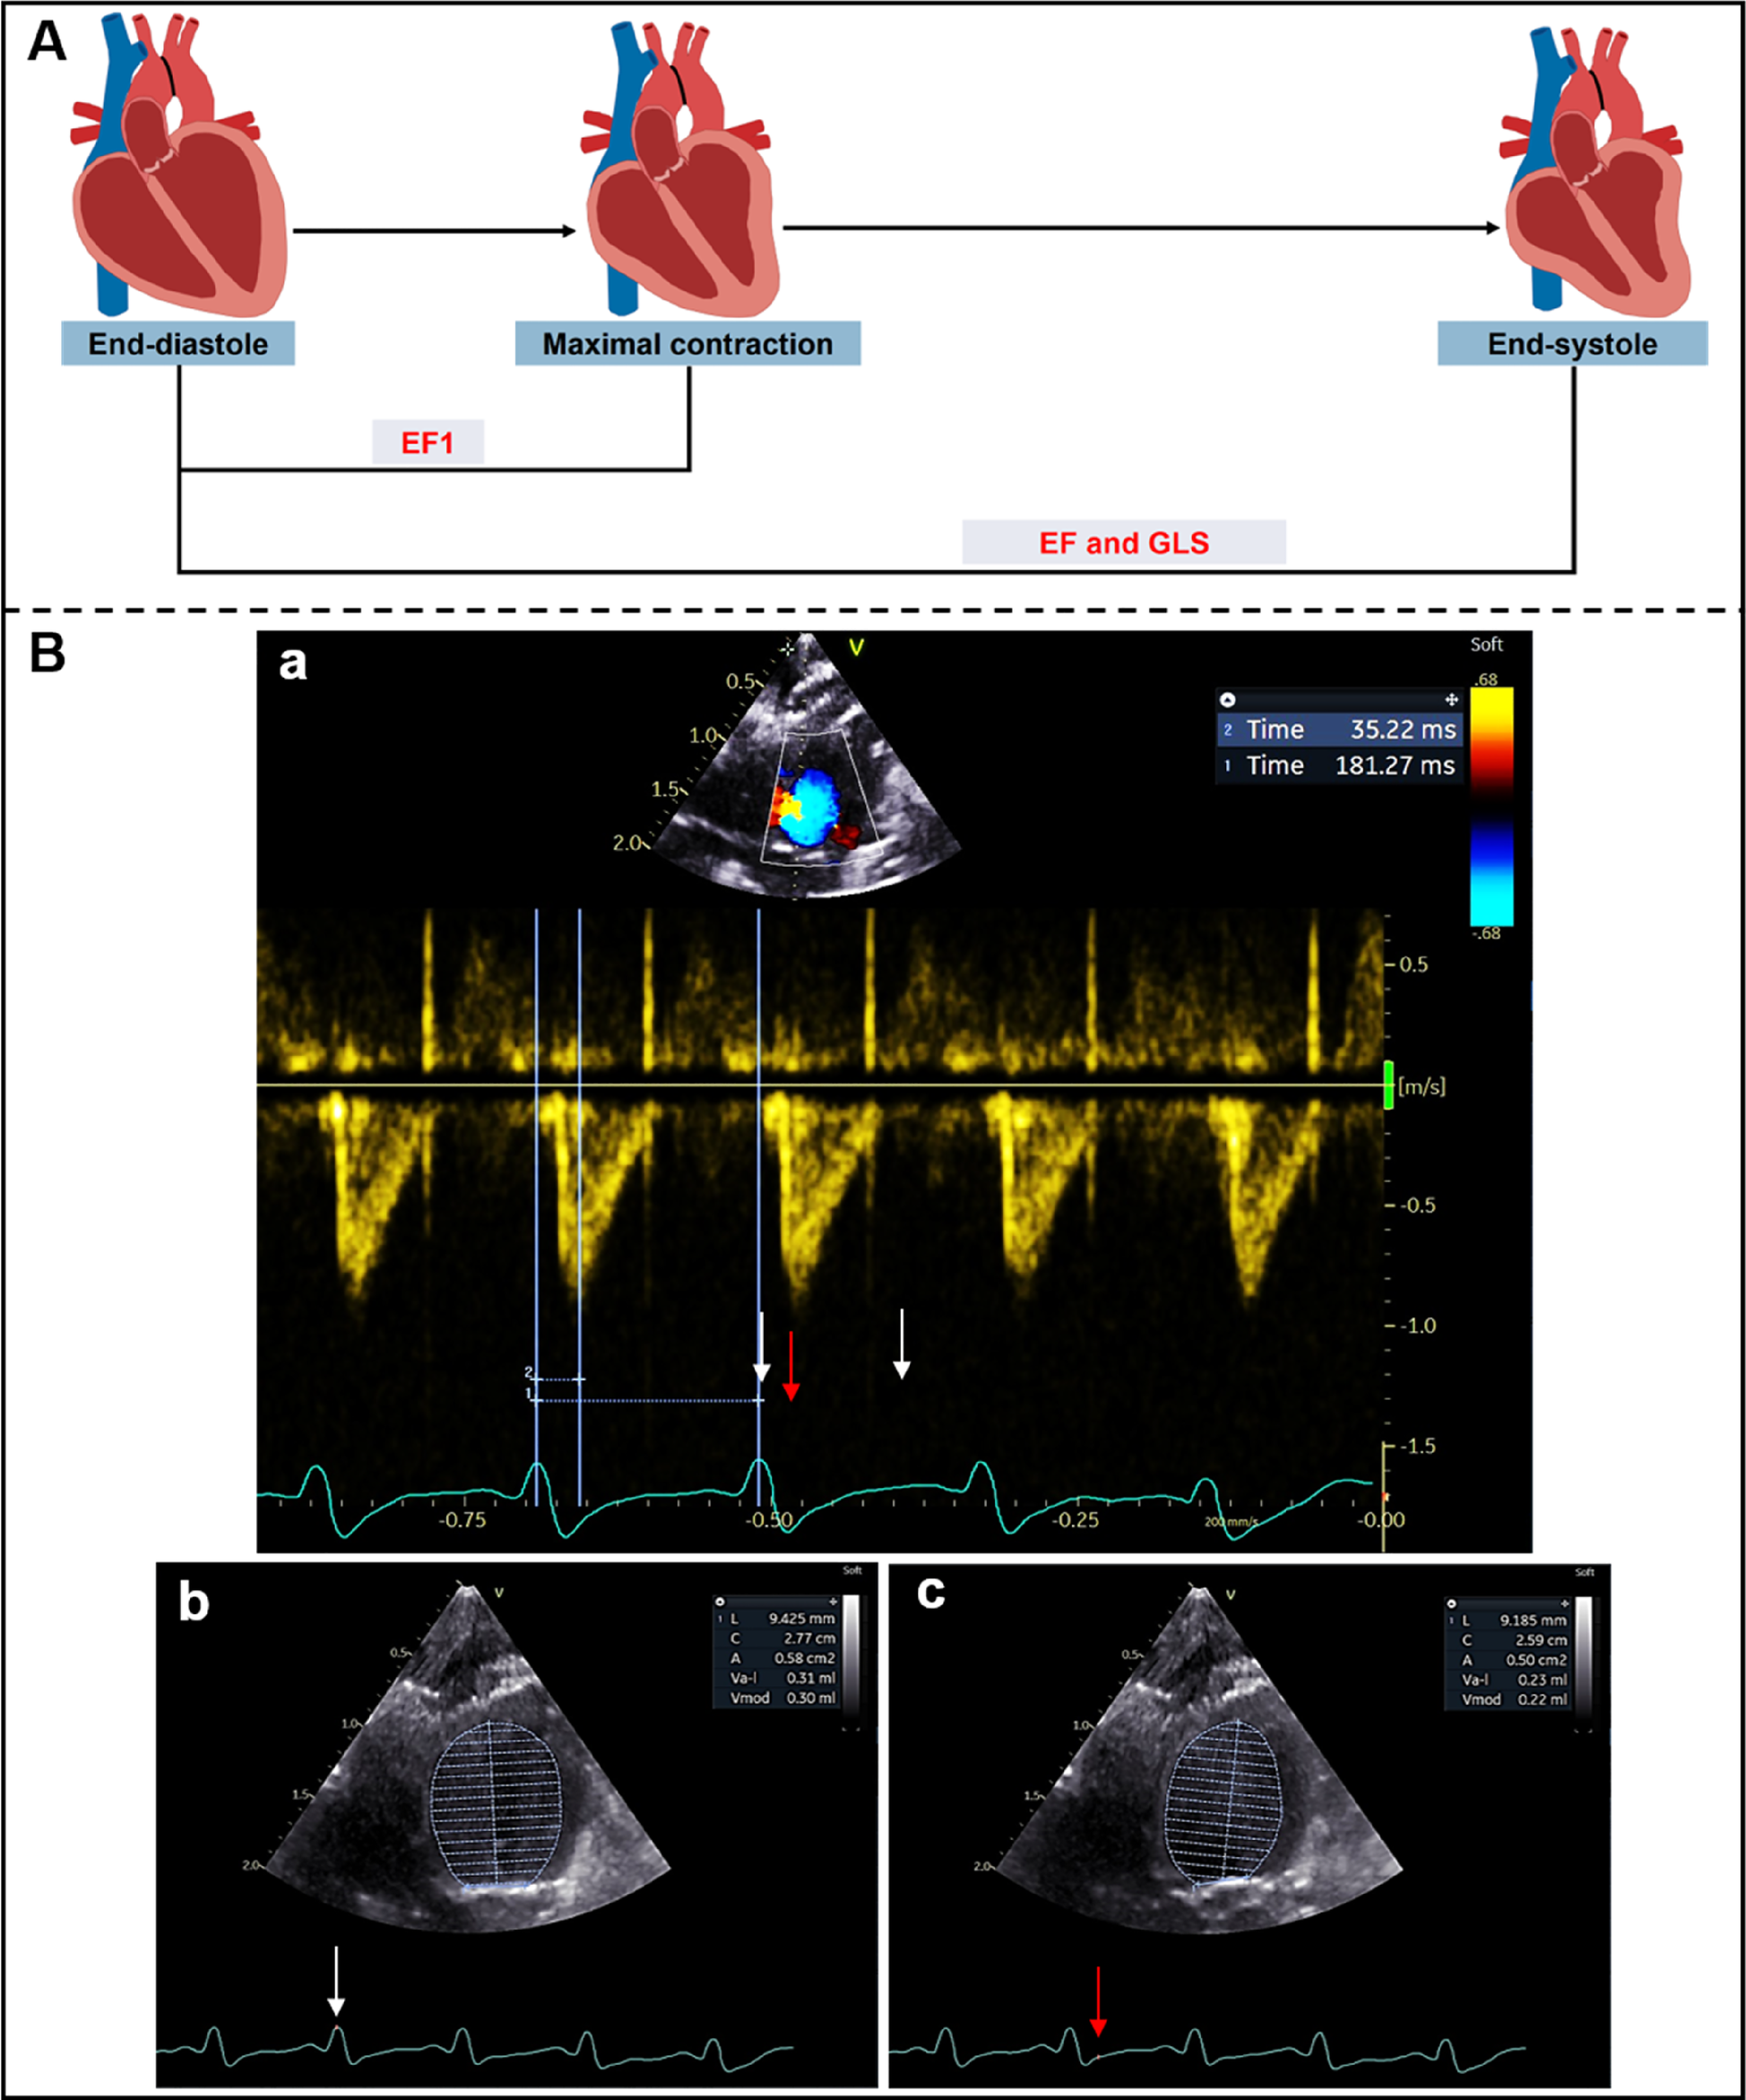

Transthoracic echocardiography was performed using a Vivid E95 ultrasound system with a 12S probe and an EchoPAC workstation (Version 204, GE Medical Systems, Milwaukee, WI, USA). Briefly, rats were anesthetized with 1.5%–2% isoflurane before echocardiography and positioned in the supine position at room temperature. Continuous-wave Doppler imaging was performed to determine the peak flow velocity and mean pressure gradient (MPG) after operation at the aortic arch, and to measure the time to peak aortic valve flow (TAVPF) and ECG R-R interval in the apical five-chamber view. Cardiac systolic function was measured in rats at different time points. The end-diastolic volume (EDV), left ventricular volume at the time of peak AV flow (V1) and end-systolic volume (ESV) were measured by Simpson's method at the apical four-chamber view. EF1 was calculated as the percentage change in left ventricular volume from end-diastole to the time of peak aortic flow velocity [EF1 = (EDV-V1)/EDV × 100%] (Figures 1A,B). EF was calculated as EF = (EDV − ESV)/EDV × 100%.

Figure 1

(A) Schematic diagram of left ventricular myocardial movement during systole; (B) EF1 was measured using Simpson's method from apical four-chamber view. ECG R-R interval (181 ms) (white arrows) and R to time of peak aortic flow velocity (35 ms) (red arrow) were measured from aortic valve continuous-wave Doppler (a), end-diastolic volume (0.30 ml) (b) and volume at time of aortic valve flow velocity (0.22 ml) (c) were used to calculate EF1 (27%).